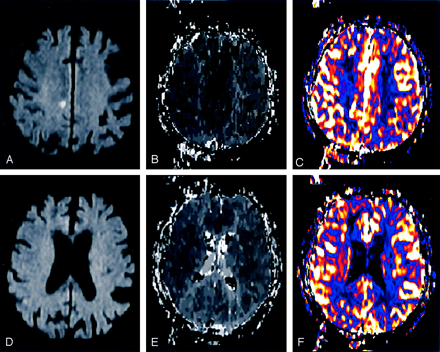

MR imaging 2 hours after the onset of stroke.

A and D, Acute MR imaging with two representative sections of DW imaging revealing a small lesion in the subcortical white matter (A, arrow), suggesting hemodynamic infarction.

B and E, Acute MR imaging with the same sections of TTP, demonstrating a perfusion delay in almost the entire right MCA territory and in both ACA territories.

C and F, Acute MR imaging with the same sections of CBF showing a decrease of cerebral blood flow in almost the entire right MCA territory and in both ACA territories, matching the TTP results.

MR diagnostics 2 hours after the onset of stroke were performed on a 1.5-T system (Siemens Magnetom Sonata, Erlangen, Germany) including fluid-attenuated inversion recovery (FLAIR), T2*-weighted imaging, DW imaging, PWI (time-to-peak [TTP] and cerebral blood flow [CBF]), TOF, and CE-MRA. Total acquisition time for MR imaging was 25 minutes. The DW imaging revealed a small lesion in the subcortical white matter of the right hemisphere without any cortical lesions (Fig 1A). Intracranial TOF only faintly visualized the right distal internal carotid artery (ICA) and the right middle cerebral artery (MCA), which suggested a proximal ICA occlusion. Supplementary CE-MRA confirmed a high-grade stenosis (>90%) of the proximal right ICA (Fig 2A) and a moderate stenosis (50%) of the left ICA. Intracranially, the A1 segment of the left anterior cerebral artery (ACA) and the right posterior communicating artery were absent. These findings suggested a dominant perfusion of both ACA territories by the stenotic right ICA. A subsequent PWI (TTP and CBF) demonstrated a substantial delay and decrease of perfusion in almost the entire right MCA territory, as well as in both ACA territories (Fig 1B, -C, -E, -F). In summary, MR imaging findings revealed hemodynamic stroke origin without peripheral embolic occlusions. Therefore, intravenous thrombolysis was not performed.